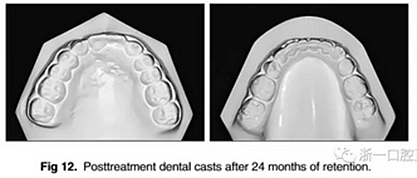

治療持續(xù)3年,患者始終保持積極和合作。口腔衛(wèi)生很好。患者和她的父母都對結(jié)果感到滿意。經(jīng)過24個月的保持后,咬合保持得很好(圖11 ; 圖12)。在上牙弓中,應(yīng)用固定舌側(cè)保持器以防止任何復(fù)發(fā)傾向。在下牙弓中,治療后拔除第三磨牙。